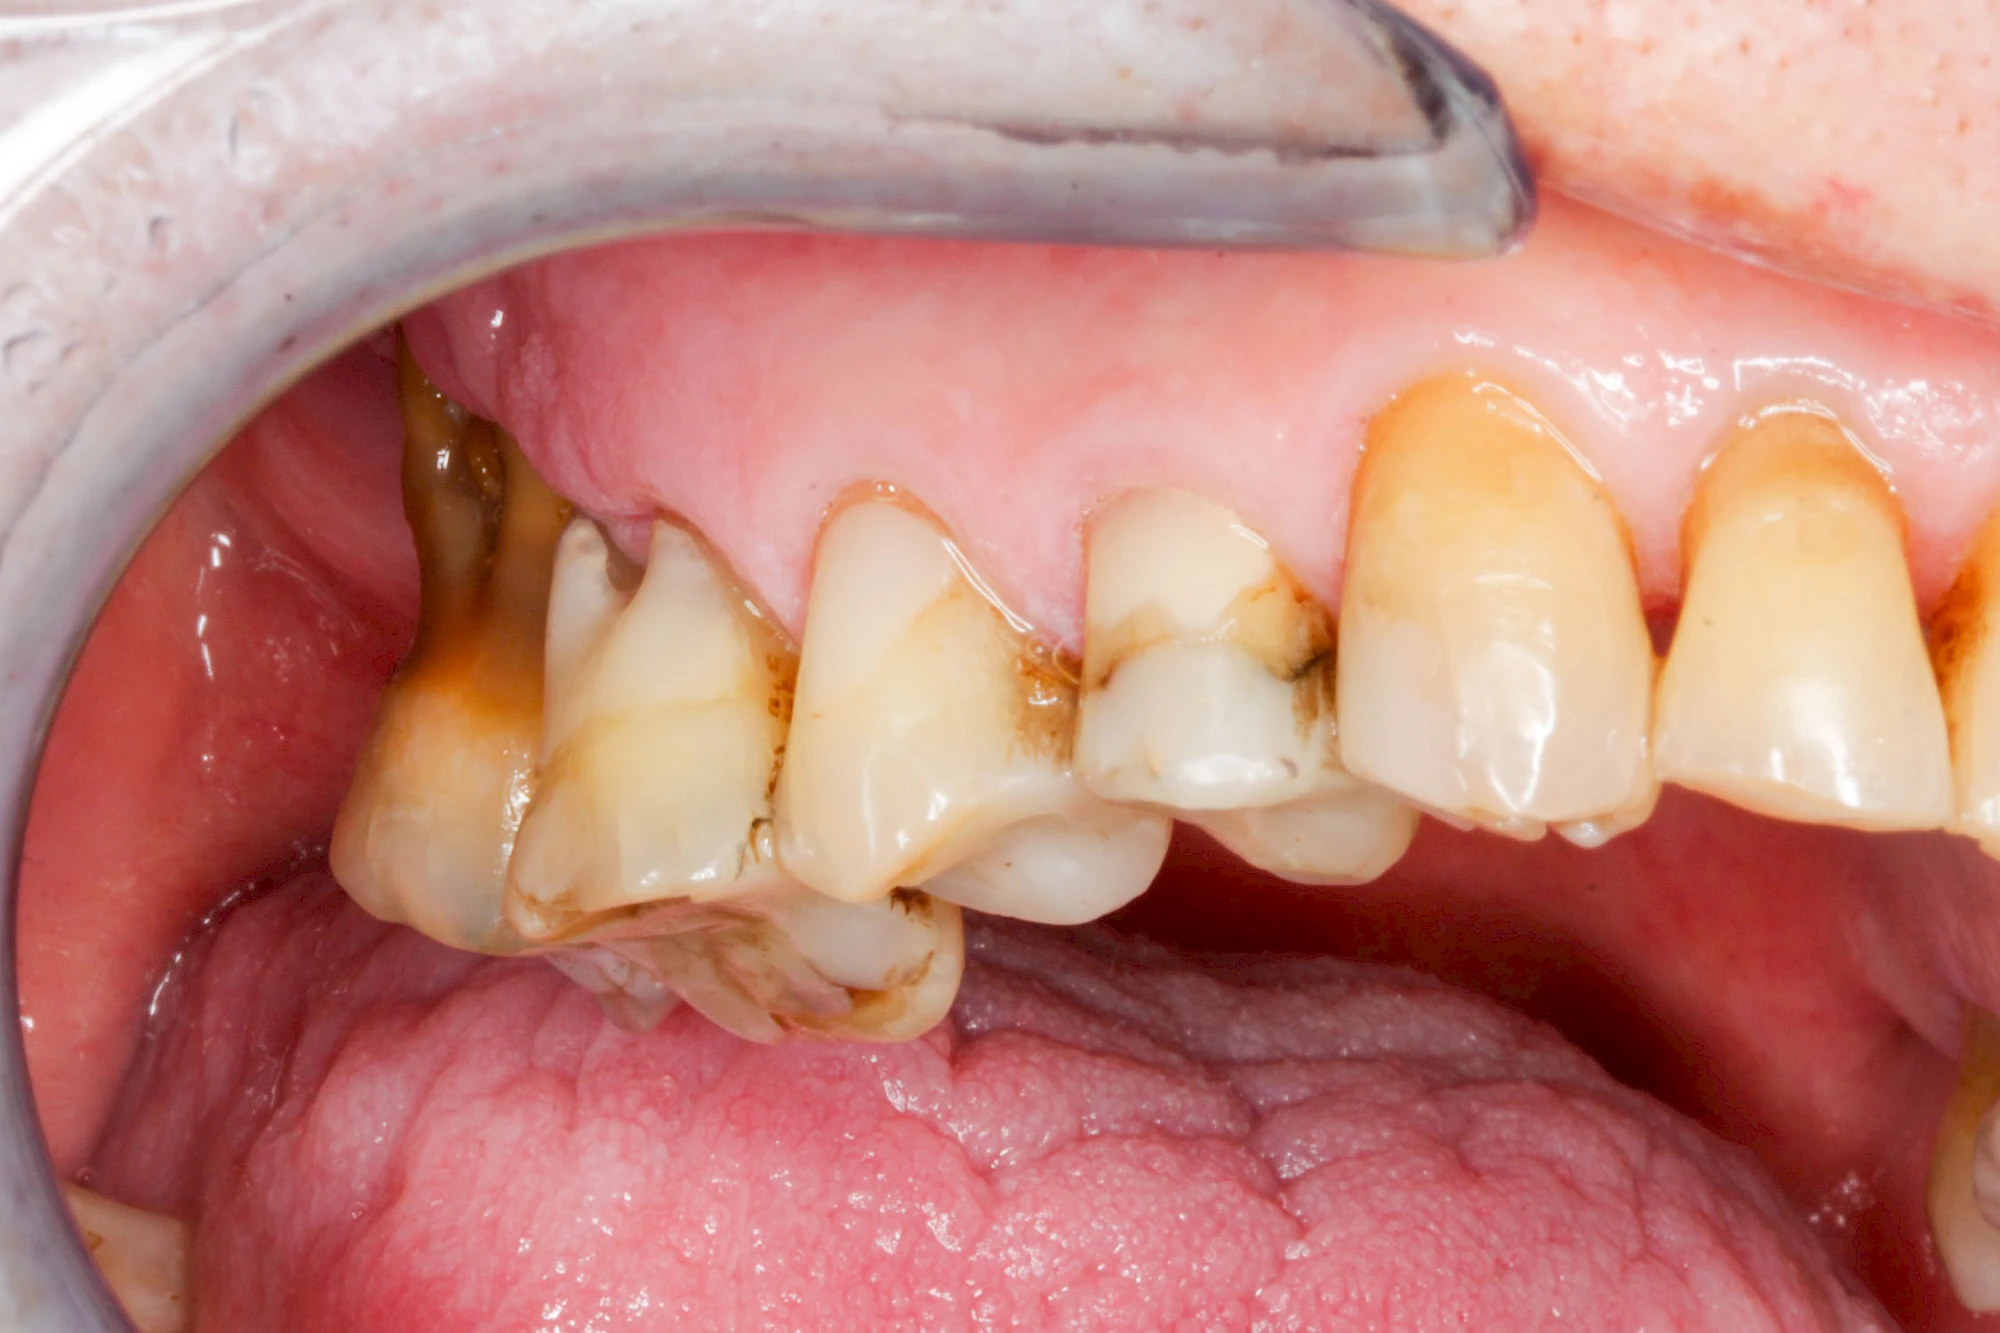

Gingivitis & Parodontitis: Stadien

Ist zunächst nur das Zahnfleisch von der Entzündung betroffen, spricht man von Gingivitis. Später, wenn auch der Knochen um die Zähne herum entzündet ist, spricht man von einer Parodontitis. Bei der Parodontitis wird der Knochen nach und nach abgebaut und das Zahnfleisch zieht sich zurück. Die Zahnhälse und Zahnwurzeloberflächen liegen mehr und mehr frei. Die Zähne werden zunehmend lockerer und fallen schließlich aus.

Bakterien in den Zahnbelägen greifen neben den Zähnen auch das Zahnfleisch (Gingiva) und den gesamten Zahnhalteapparat (Parodont) an. Der Körper reagiert mit einer Entzündung, sichtbar als Rötung und Schwellung. Meist blutet das Zahnfleisch z .B. beim Essen oder auch beim Putzen der Zähne.